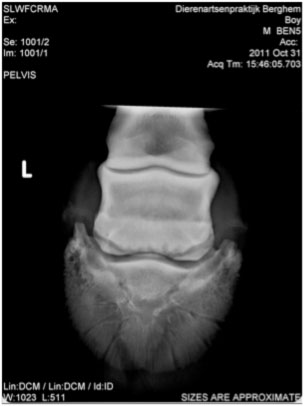

Example: 7-year-old Dutch Warmblood.

History: This horse was suffering from severe navicular disease as a 6-year-old, was extremely lame and was given up. As a last resort the horse was put on the Vitafloor twice daily initially and on improvement, reduced to treatment once a day.

Impressions: Photo on the right was taken 14 months after photo on the left. According to the veterinarian, the number of ‘lollipops’ has reduced (visible on originals on HD screen).